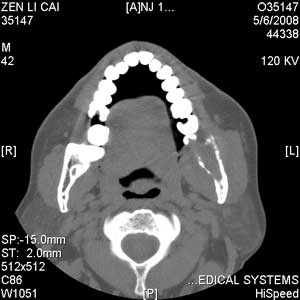

以下是引用jiangjing在2008-5-28 15:56:00的发言:[br]下颌骨左侧部骨质破坏,轻度膨胀,瘤骨形成,软组织肿胀考虑 恶性骨肿瘤-----肉瘤类